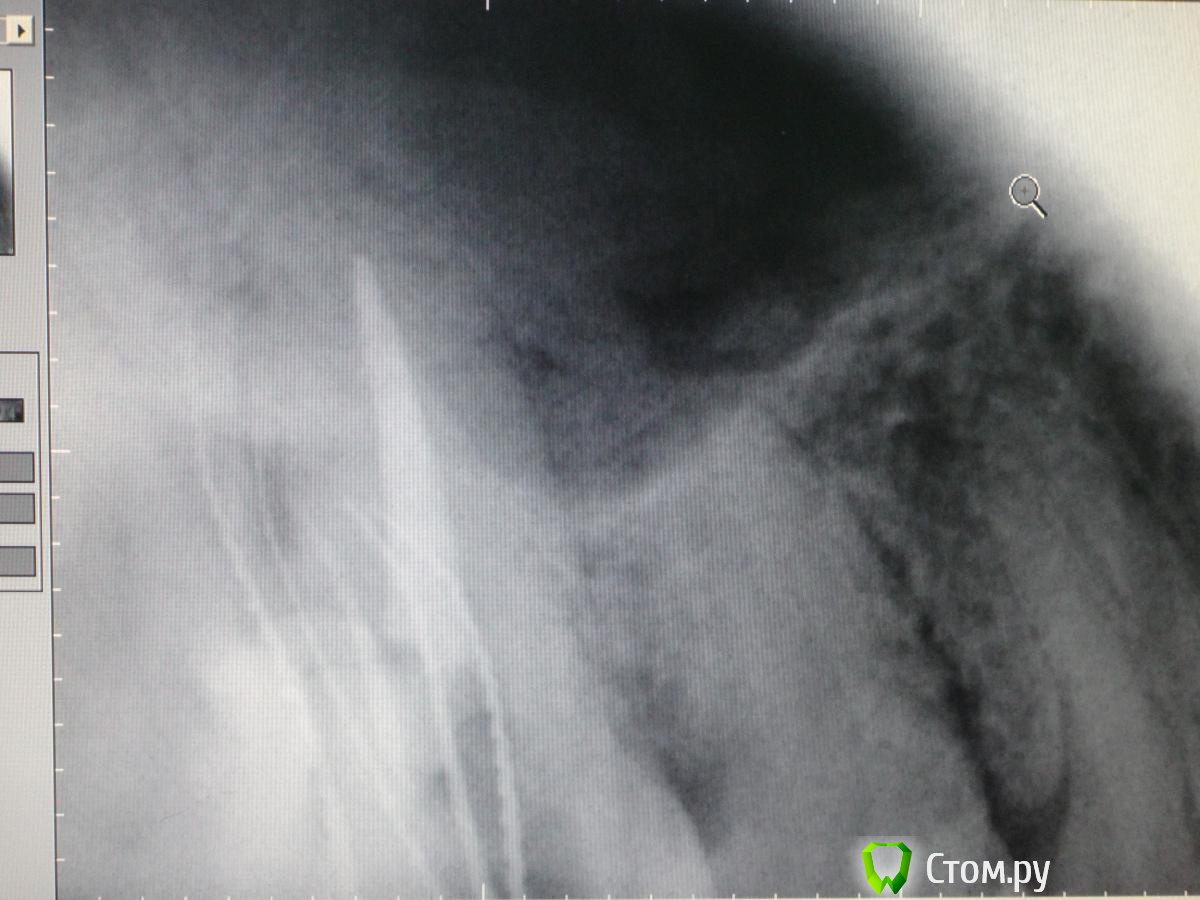

Slaggy Опубликовано 6 ноября, 2014 Автор Поделиться Опубликовано 6 ноября, 2014 Кейс некрасивый. Но какой уж есть.За качество снимков дико извиняюь. Мой рекордсмен: Пациент обратился по гарантии в клинику. 16ый зуб. Жалобы периодонтитные.снимок 2 месяца назад - Пломба поразила своей оригинальностью ((( - не суть.нашел каналы - временная пломба - Запломбировал - Шесть каналов - 3 в МВ системе, 2 в DB и небный. Вернул нашлепку на место. Обычно отправляю к доктору - виновнику торжества на пломбировку, но тут решил, что через недельку обточу и коронку, потому что МОД полость, глубоко, пломба - на снимке во всей красе. Если полностью убрать и переделать - все одно под коронку.Снимки без коффера, сделаны после снятия оптрадама. 4 Ссылка на комментарий

Slaggy Опубликовано 22 ноября, 2014 Автор Поделиться Опубликовано 22 ноября, 2014 (изменено) С "неаккуратным зубом" - откинул, заполировал, ушил, времянка. Фоткать некогда было, может на следующих этапах. Свеженькая находка 5 в шестом Кальций, тефлон, септопак - из-за недостатка времени. Снимки сам стал делать ))) пока кривенько. Изменено 22 ноября, 2014 пользователем Slaggy 2 Ссылка на комментарий